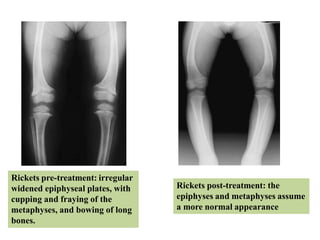

Rickets pre-treatment: irregular

widened epiphyseal plates, with

cupping and fraying of the

metaphyses, and bowing of long

bones.

Rickets post-treatment: the

epiphyses and metaphyses assume

a more normal appearance